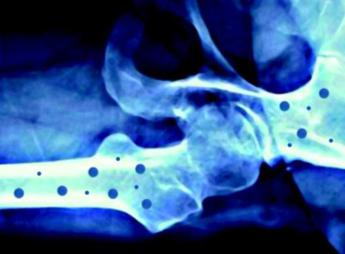

(Adnkronos) – In occasione della Giornata mondiale dell’osteoporosi, che si celebra il 20 ottobre sul tema ‘Dite no alle ossa fragili', Feidos, Federazione italiana osteoporosi e malattie dello scheletro, rinnova il suo impegno per la salute delle ossa con nuove iniziative a supporto dei pazienti. L’osteoporosi – ricorda una nota – è una patologia che colpisce almeno 5 milioni di persone in Italia e 200 milioni nel mondo, e la cui incidenza è destinata a crescere nel prossimo futuro. Su questa malattia ormai globale, Feidos accende i riflettori sensibilizzando la popolazione sull’importanza di adottare sani stili di vita per migliorare lo stato di salute delle ossa, in particolare attraverso una corretta alimentazione, un’adeguata e regolare attività fisica, nonché prestando attenzione ai fattori di rischio individuali. Nelle giornate del 20 ottobre, ad esempio, si potrà richiedere un consulto telefonico gratuito con un medico specialista chiamando il Numero Verde 800 909225 e, recandosi presso uno degli ambulatori aderenti all’iniziativa elencati sul sito fedios.org, si potrà accedere a un controllo gratuito del rischio di osteoporosi. L’impegno di Feidos è quello di garantire ai pazienti un supporto continuo attraverso campagne d’informazione, impiego di volontari presso le strutture ospedaliere, indagini con l’obiettivo di individuare bisogni, criticità ed eventuali buone pratiche per facilitare l'accesso alle terapie più appropriate. Anche quest’anno la Federazione consolida la partnership con l’associazione pazienti Mamog, Mamme con osteoporosi gravidica. L’obiettivo comune è di fornire informazioni circa questa patologia che causa fratture spontanee durante l’ultimo trimestre di gravidanza e nel puerperio. Sempre a sostegno dei soggetti affetti da osteoporosi, Feidos inaugura anche il legame con un nuovo partner, il gruppo Ffn, Fragility fracture network Italia, la parte italiana di un’organizzazione internazionale, la Ffn che ha come obiettivo quello di creare una rete multidisciplinare di esperti per ottimizzare la gestione e la prevenzione secondaria delle fratture da fragilità.

L’iniziativa ha il supporto incondizionato di Ibsa Farmaceutici Italia come main sponsor, e di Gedeon Richter, Organon, Accord Healthcare Italia, Ucb e Theramex come silver sponsor. Sono le aziende farmaceutiche che hanno scelto di sostenerne questi importanti progetti di informazione che, grazie a loro, possono essere portati avanti. L’osteoporosi – conclude la nota – è una malattia sistemica dell'apparato scheletrico, caratterizzata da una bassa densità minerale e dal deterioramento della micro-architettura del tessuto osseo, con conseguente aumento della fragilità ossea e del rischio di fratturarsi. —salutewebinfo@adnkronos.com (Web Info)